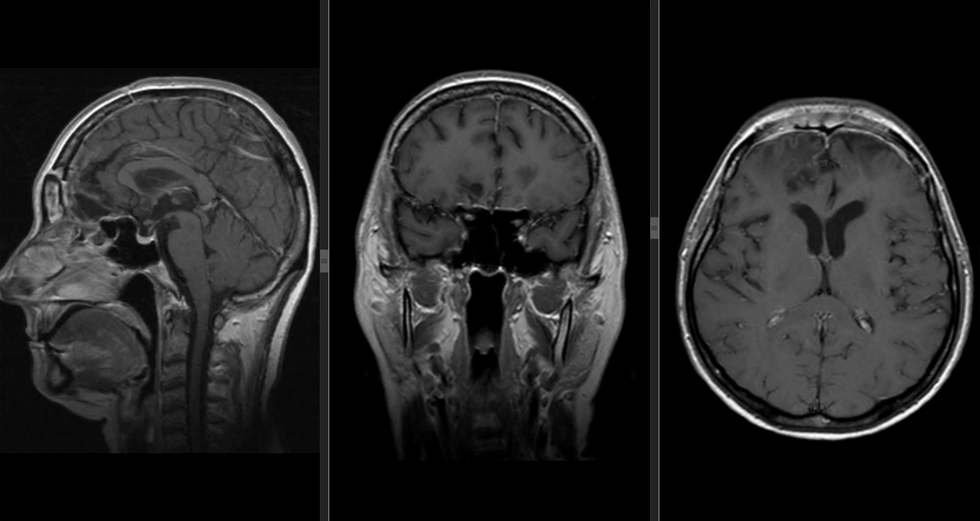

Професор Володимир Смоланка пояснює: «Пухлина була гігантських розмірів – більше 6 сантиметрів у діаметрі й локалізувалася у риноольфакторній ямці, тобто це ділянка носа й очей. Вона була небезпечною для життя пацієнтки. Складність була ще й у тому, що вона проросла через два зорові нерви та кілька судин: передню сполучну артерію й обидві сонні артерії. Якщо пошкодити одну з цих судин, у післяопераційному періоді в пацієнта буде обширний ішемічний інсульт із високим ризиком смерті. Цікаво, що для таких утворів серед іншого характерна клініка – порушення нюху. Через пандемію COVID-19 пацієнтка могла не звернути на це увагу. Ми з командою видалили пухлину одним етапом і післяопераційне МРТ показало тотальне видалення. Гістологія підтвердила, що, як ми й передбачали, це менінгіома – доброякісна пухлина».